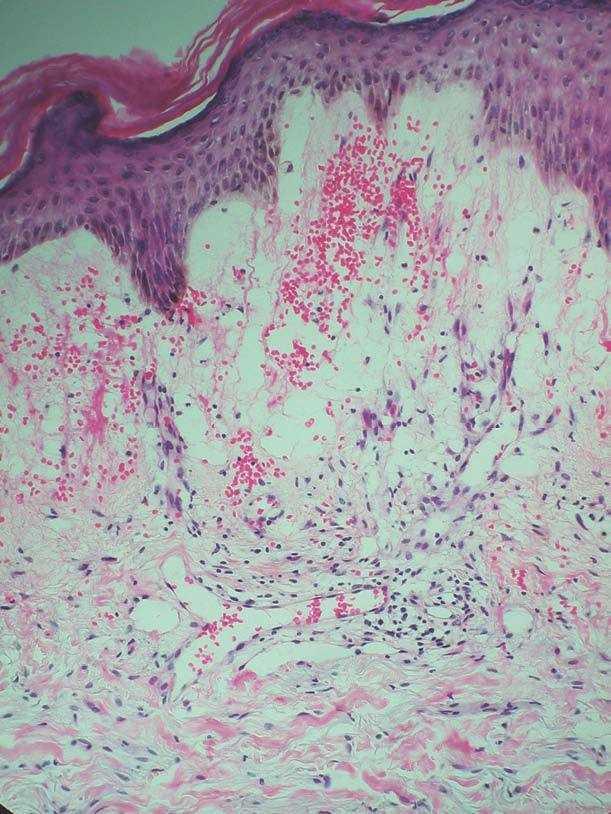

Paciente de 67 años de edad con antecedentes de hipercolesterolemia y anexectomía derecha con ligadura tubárica en 1993. Es intervenida de un carcinoma intraductal de la mama izquierda (T1N0M0) en 1992, por lo cual sufrió una cuadrantectomía superior izquierda junto con una linfadenectomía axilar profiláctica y tratamiento complementario con radioterapia y hormonoterapia (letrozol). En 2004 comienza con lesiones en el miembro superior izquierdo junto con dolor y edema de dicha extremidad. Fue diagnosticada inicialmente de celulitis, recibiendo tratamiento con amoxicilina más ácido clavulánico con mala evolución del cuadro, momento en el cual es valorada por dermatología. La paciente presentaba un importante edema en la extremidad superior izquierda, junto con múltiples pápulas eritematosas de superficie brillante bien definidas (fig. 1). Las lesiones eran asintomáticas y no se habían modificado desde su aparición. Se procedió a la realización de una biopsia cutánea que presentaba múltiples cavidades en dermis papilar y reticular alta que producían una dehiscencia a dicho nivel. Dichas cavidades estaban ocupadas por un material eosinofílico y recubiertas por una capa de células endoteliales que correspondían a vasos linfáticos (fig. 2). Se estableció de esta forma el diagnóstico de linfangiectasias. Las lesiones se resolvieron espontáneamente al cabo de unas semanas, persistiendo el edema de fondo.

Figura 1. Pápulas eritematosas en extremidad superior.